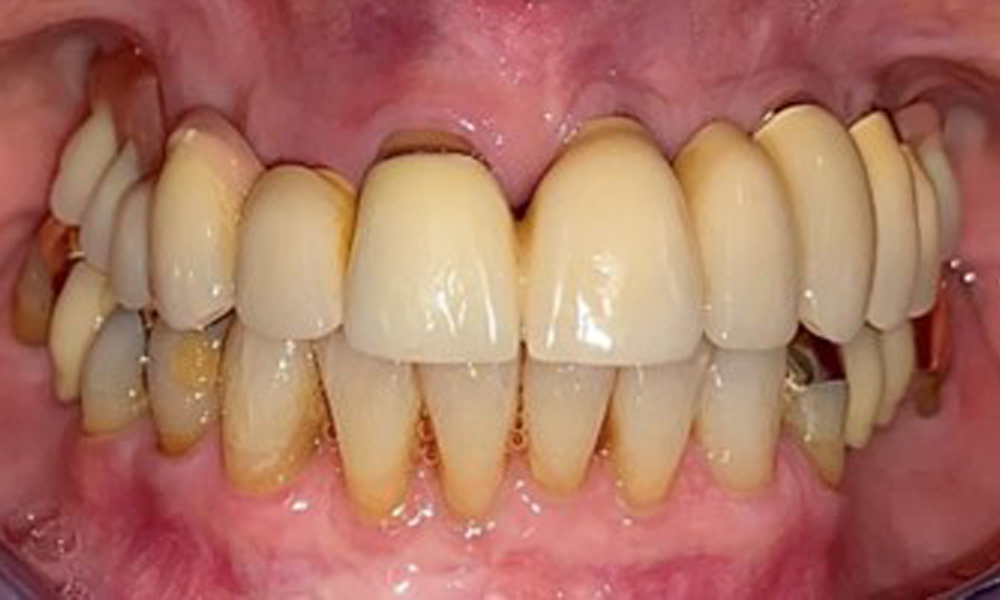

Frontalansicht mit dem eingesetzten Zahnersatz im Oberkiefer.

Abb. 1: Frontalansicht mit dem eingesetzten Zahnersatz im Oberkiefer.

Die Patientin wurde vor über 25 Jahren mit einer kombinierten herausnehmbare Implantat-Teleskopprothese im Oberkiefer versorgt (Abb. 1, Abb. 2, Abb. 3) und ist sehr glücklich über ihren Zahnersatz. Im Unterkiefer hat die Patientin einen suffizienten festsitzenden Zahnersatz. (Abb. 4)

Der dentale Befund stellt sich wie folgt dar: Kombinierte herausnehmbare Implantat- und zahngetragene Teleskoparbeit auf Implantaten 15, 13, 21, 23, 24, 25 und Zahn 11 (Abb. 1, Abb. 2, Abb. 3). Im Unterkiefer ist die Patientin mit einem festsitzenden Zahnersatz versorgt. 37–34 sowie 45–47 haben suffiziente Brücken (Abb. 4). Kronenränder sind intakt, aktive kariöse Läsionen sind nicht vorhanden. An Zahn 43 zeigt sich eine Compositefüllung mit Randspalt. Im Unterkiefer liegen Rezessionen mit freiliegender Wurzeloberfläche zwischen 1 – 3 mm vor. Dies trifft auch für 11 zu.